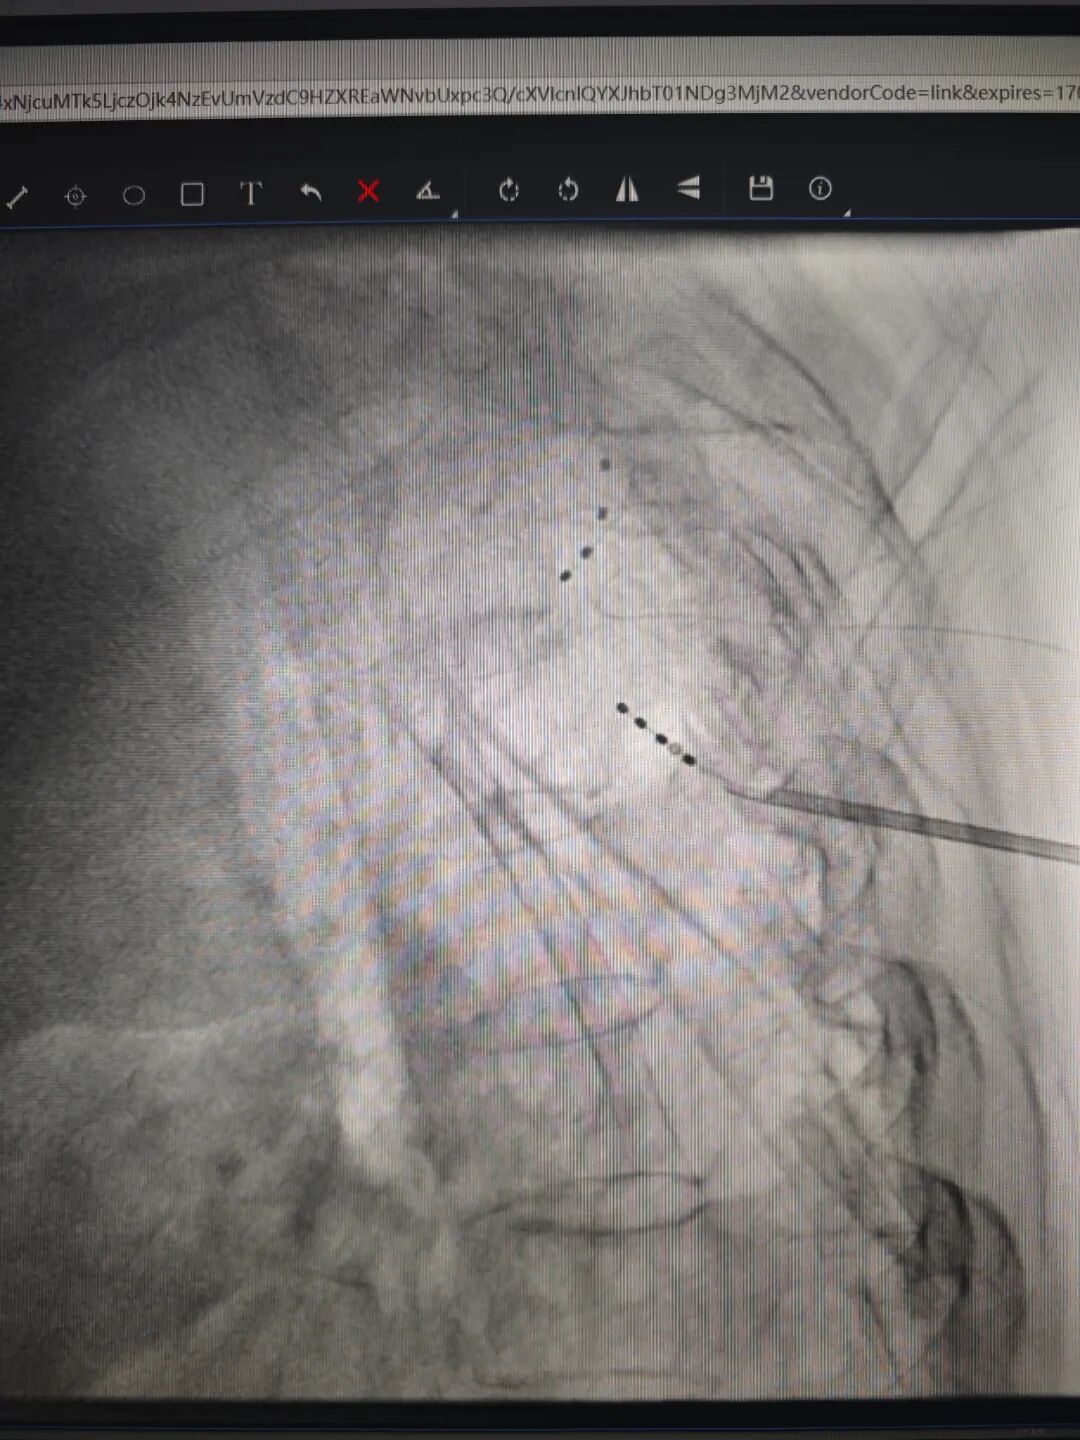

收入院后,经过评估,11月23日,黎哲敏、郑臻医生为姜阿姨进行了背根节电刺激 (dorsal root ganglion stimulation, DRGS),经过一周治疗,姜阿姨的带状疱疹后遗神经痛得到有效缓解,开心出院。

据介绍,背根节电刺激是电刺激治疗方式的一种,类似于脊髓电刺激治疗,该治疗具有刺激精准、副作用小的优势,可以避免神经调节方式的迁移和植入位置产生的副作用。